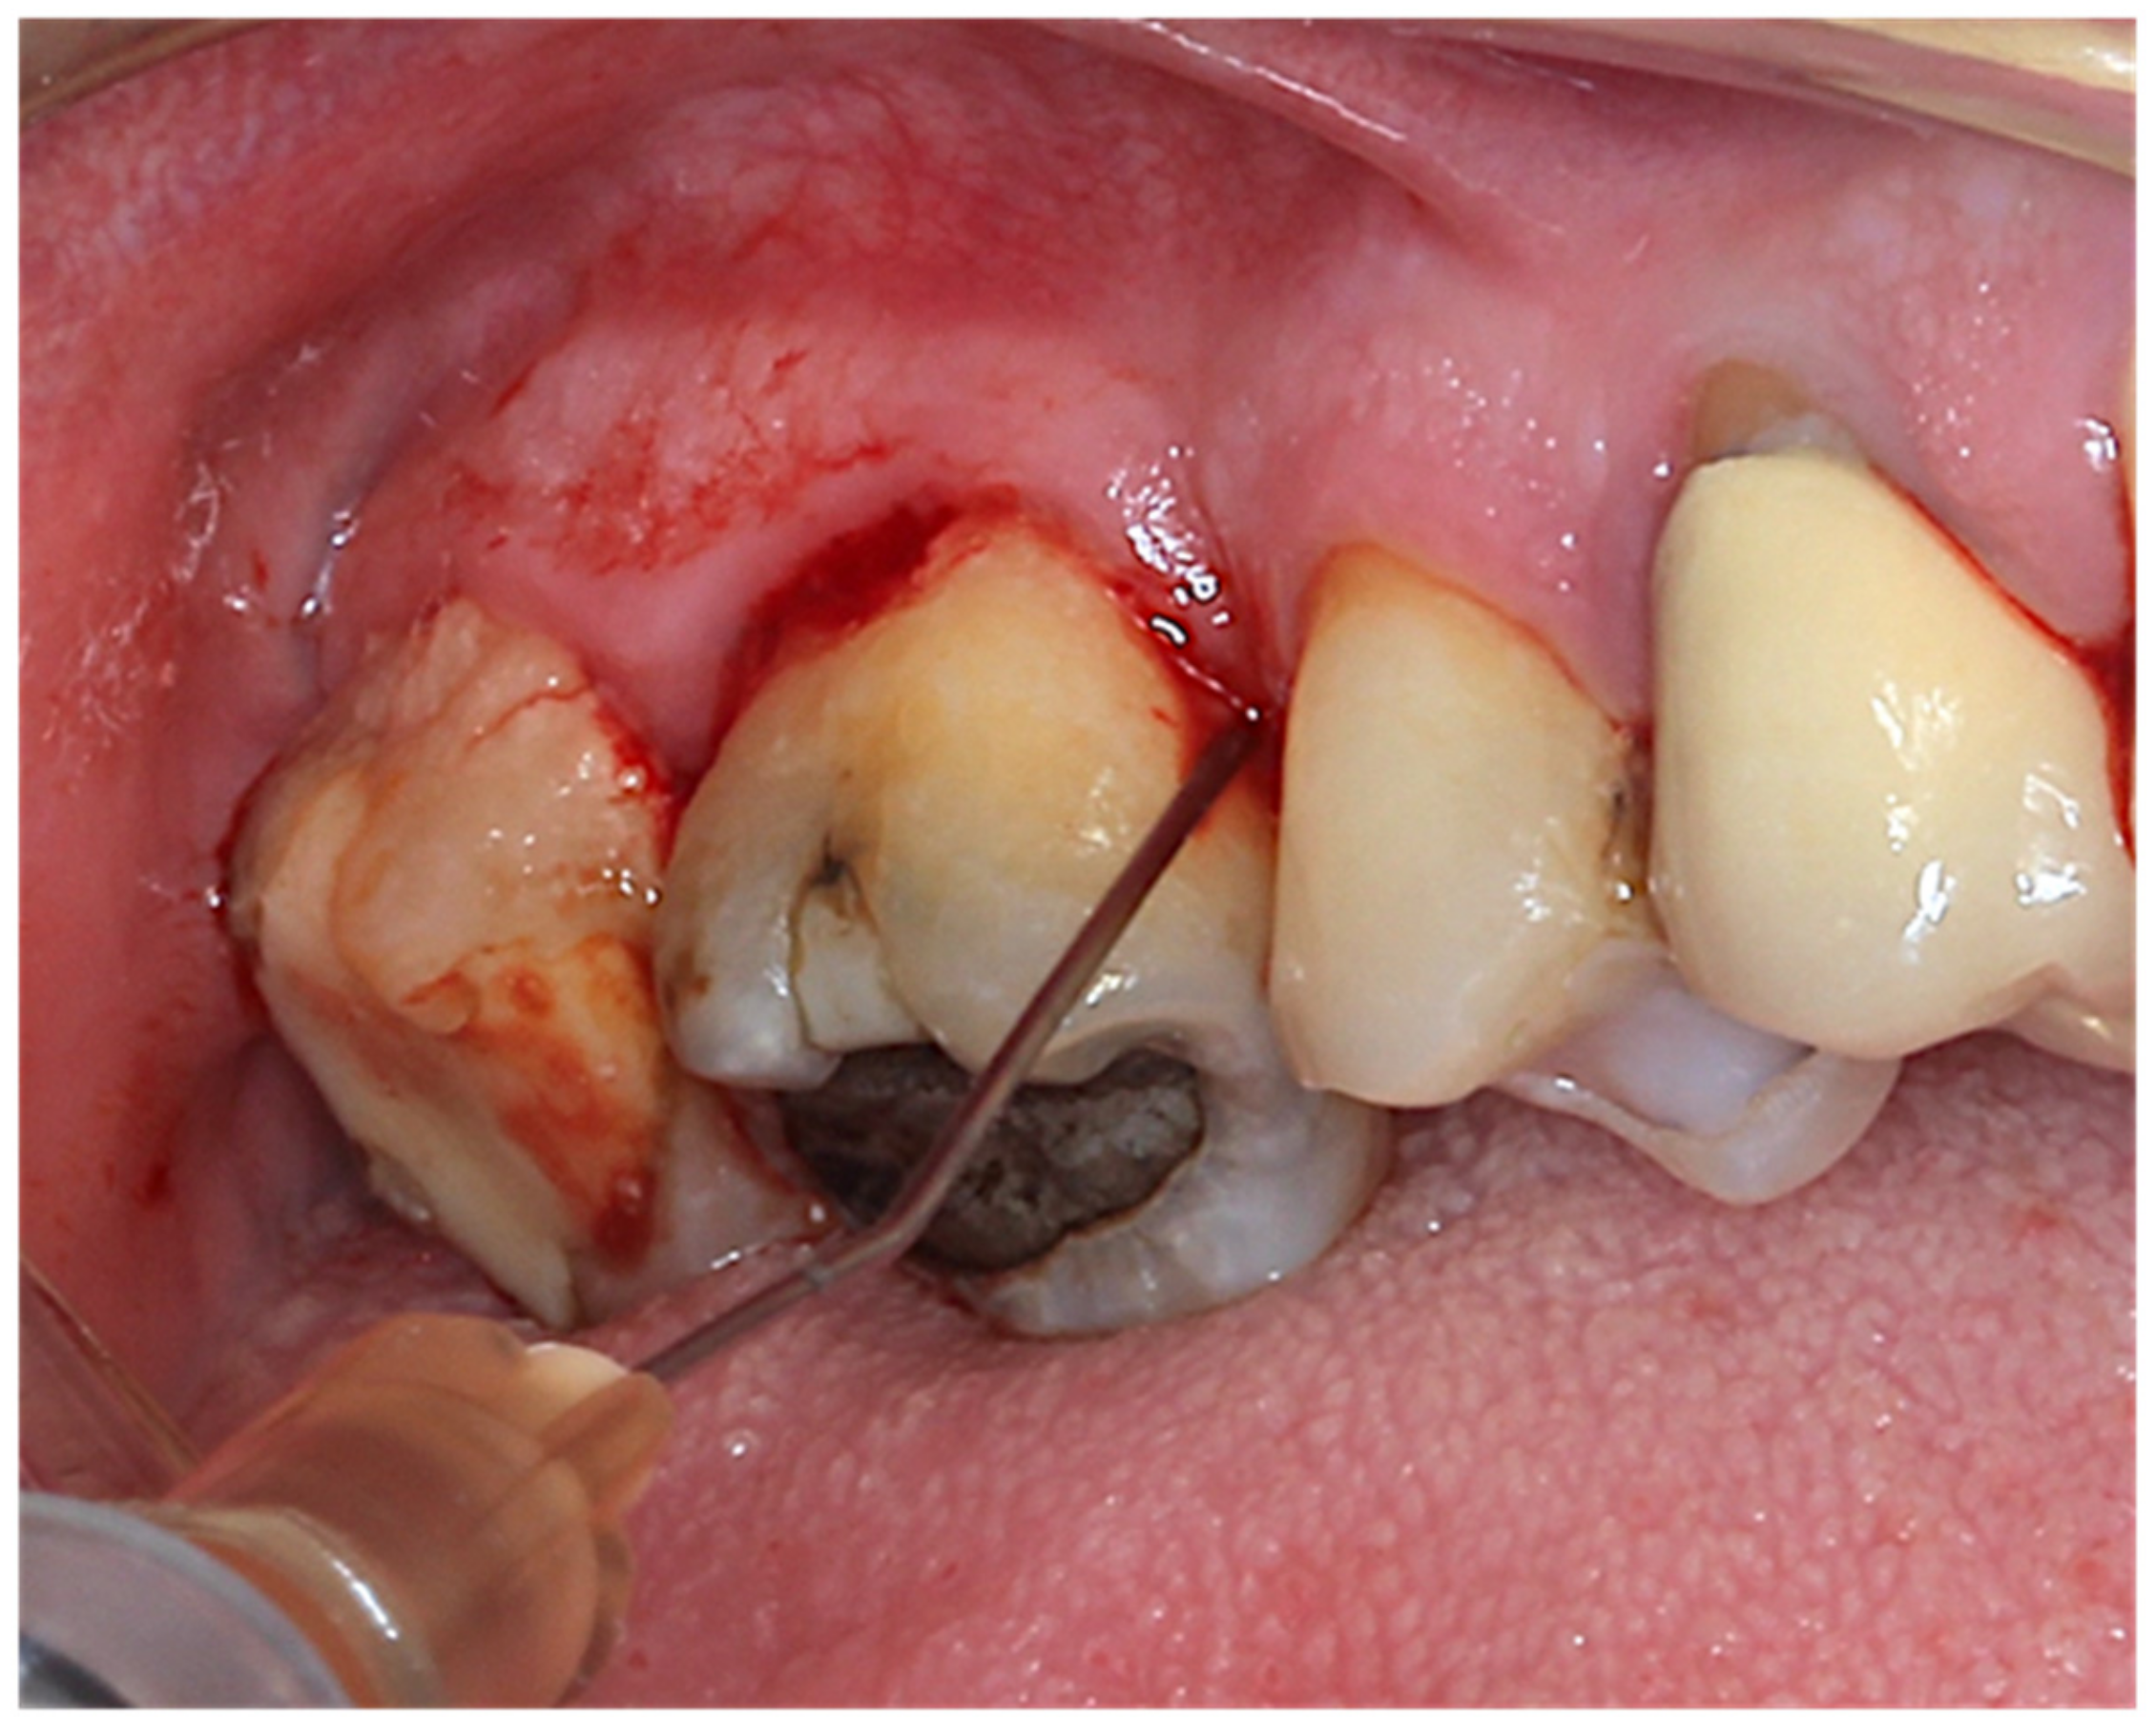

2.4. Intervention and Randomization